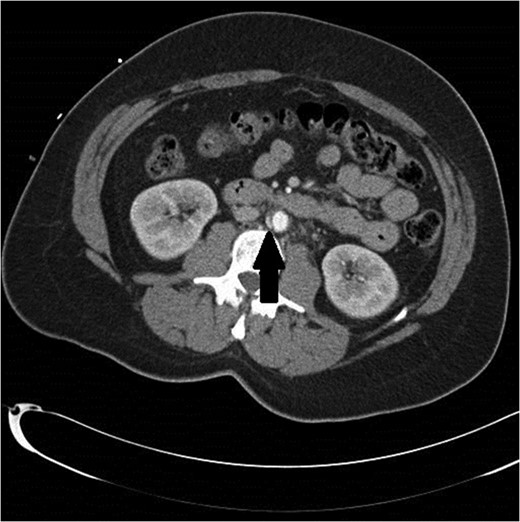

A 47-year-old woman with a history of hypertension and smoking was involved in a high-speed motor vehicle accident and presented to the emergency department with back pain. Computed tomographic (CT) scans were obtained of her abdomen and pelvis. On a single image from the abdominal scan, what appeared to be either an intimal flap or a small amount of contrast extravasation outside of the infrarenal aorta could be seen. Her care providers had differing opinions as to what was being seen on the image. Since the abnormality was only seen on a single image, the exact etiology could not be delineated (Fig. 1). The patient was observed in the hospital overnight, had minimal complaints the next day, and was discharged on aspirin.

Initial CT scan shows enhancing vascular abnormality on the right side of the aorta, shown by the black arrow.